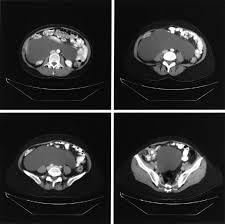

Benign Cystic Mesothelioma Of The Peritoneum In A Male Child Journal Of Pediatric Surgery

Benign Cystic Mesothelioma Of The Peritoneum In A Male Child Journal Of Pediatric Surgery from els-jbs-prod-cdn.jbs.elsevierhealth.com